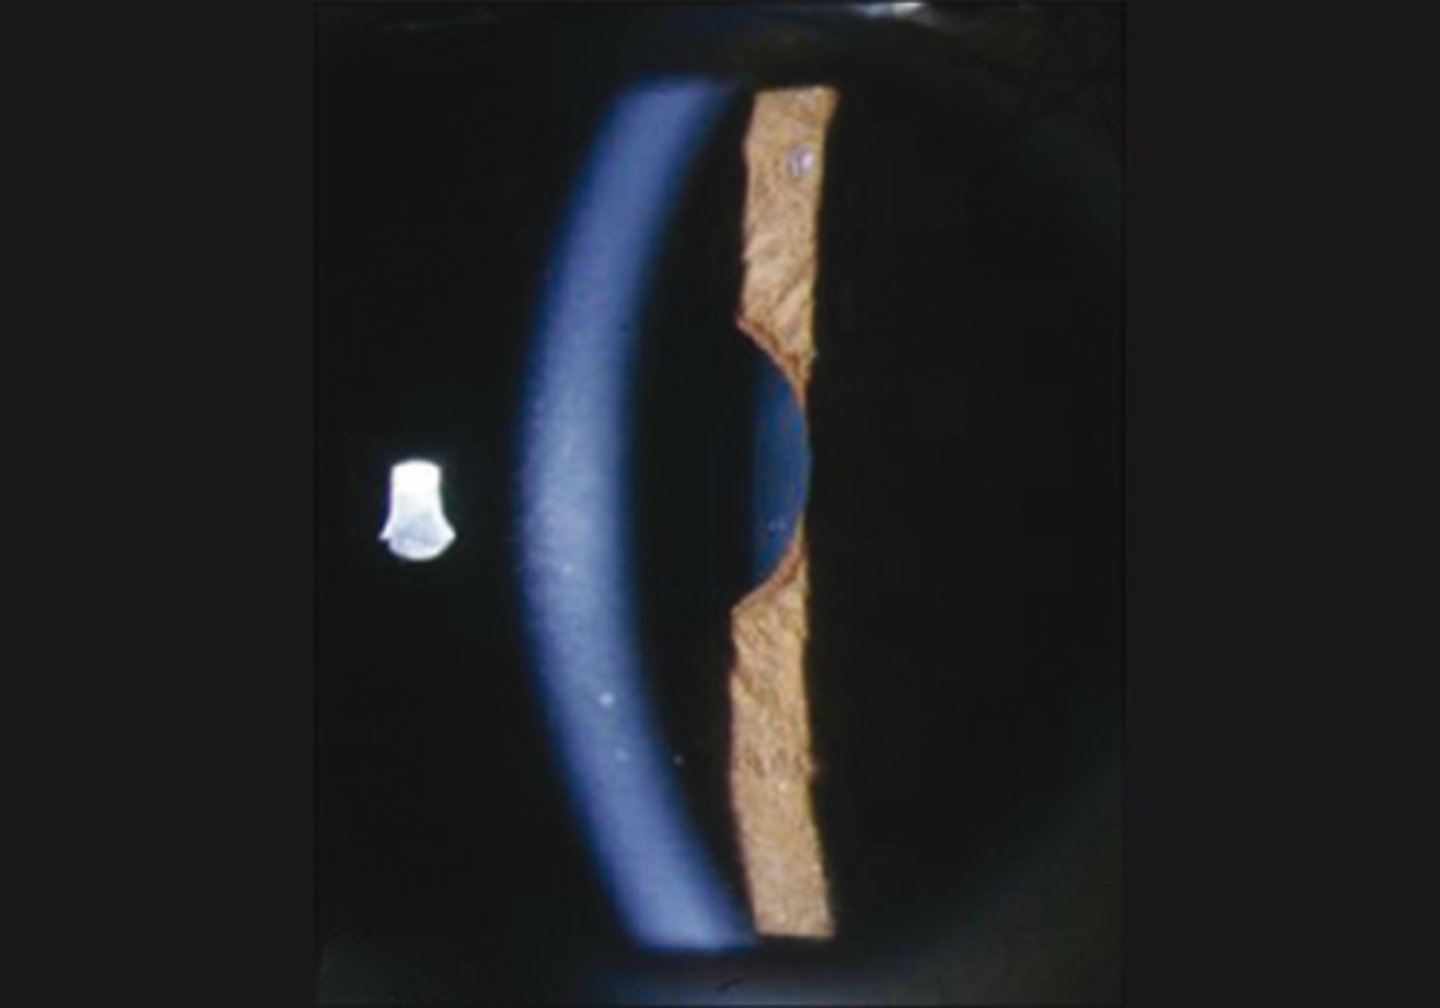

Explain the progression of the Hutchinson pupil seen in Uncal syndrome.

1. miotic pupil due to initial cerbreal edema

2. ipsilateral dilated pupil due to expanding mass on that side

3. bilateral fixed and dilated pupils eventually